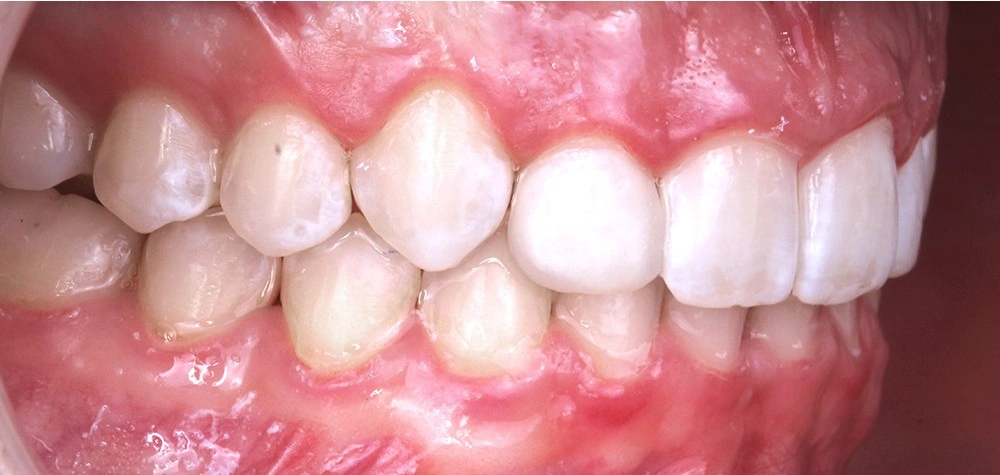

Глубокий прикус - Кейс 5

Эффективность устранения дефекта прикуса посредством элайнеров FlexiLigner.

Результаты лечения